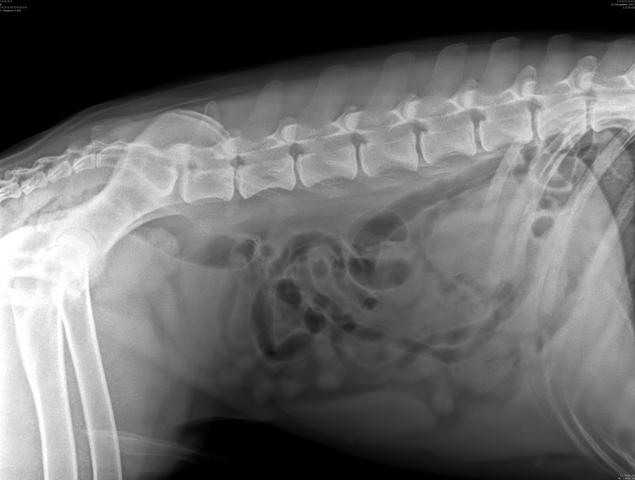

Мы делали комплексное УЗИ, оно есть в фотоархиве. И вот тут я прикрепляю. Плюс отдельно делали УЗИ сердца, почек, мочевого. Веде норма или почти норма.